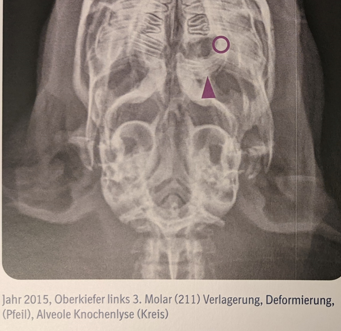

Punkt 6: zusätzlich erkennbare Patholgien finden keine Erwähnung

In der Bildbeschreibung werden lediglich die Zahnveränderungen und die Knochenlyse beschrieben, wobei der lila Kreis aber eigentlich nicht darauf hinweist. Nicht erwähnt werden die höchstgradige strukturelle Veränderung des betroffenen Backenzahnes (M3) bis in den apikalen Bereich hinein, einhergehend mit einer ausgeprägten apikalen Elongation (gelber Pfeil) sowie einer vor allem kaudal erkennbaren entzündlichen Zahnfacherweiterung (gelber gestrichelter Pfeil). Ebenso ignoriert werden die ausgeprägte apikale Elongation des M3 im rechten Oberkiefer (roter Pfeil und rote gestrichelte Linie) und eine vermutlich vorliegende Veränderung des linken Kiefergelenkbereiches (grüner gestrichelter Kreis). Der kaudale Unterkieferast liegt linksseitig viel weiter entfernt von der lateralen Wand der Bulla tympanica als auf der Gegenseite – dabei durchaus berücksichtigend, dass die Aufnahme nicht absolut symmetrisch gelagert ist. Eine Ausbreitung lokaler Infektionen vom M3 zum nahegelegenen Kiefergelenk oder der Orbita sind häufige Komplikationen. Da Pathologien des Kiefergelenkes prognostisch meist infaust sind, müssen sie Erwähnung finden. Am Besten mit einem Hinweis, wie man nun weiter vorgehen kann/soll. Die Veränderungen nicht zu erwähnen, könnte dazu verleiten den betroffenen Zahn jetzt einfach zu ziehen und eine Heilung zu erwarten, die aber unter Umständen so nicht erwartet werden kann. Komplikationen und ein fatales Ende können hierdurch vorprogrammiert werden.